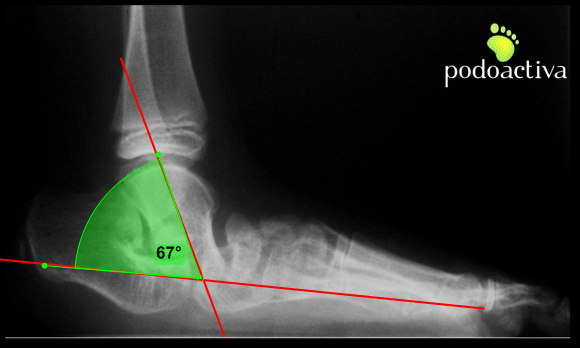

A nivel radiológico se pueden obtener medidas alteradas de diversos ángulos en proyecciones dorsoplantar y sagital. Prestaremos especial atención al ángulo radiográfico sagital TAMBA:

– El ángulo del eje del astrágalo con la base del primer metatarsiano (TAMBA):

– Entre 30º y 60º lo consideraremos astrágalo oblicuo.

– Valores por encima de 60º los consideraremos astrágalo vertical.